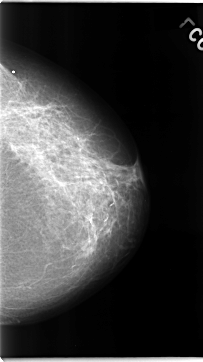

C_0072_1.RIGHT_CC

RIGHT_MLO LINES 4656 PIXELS_PER_LINE 2688 BITS_PER_PIXEL 12 RESOLUTION 50 NON_OVERLAY